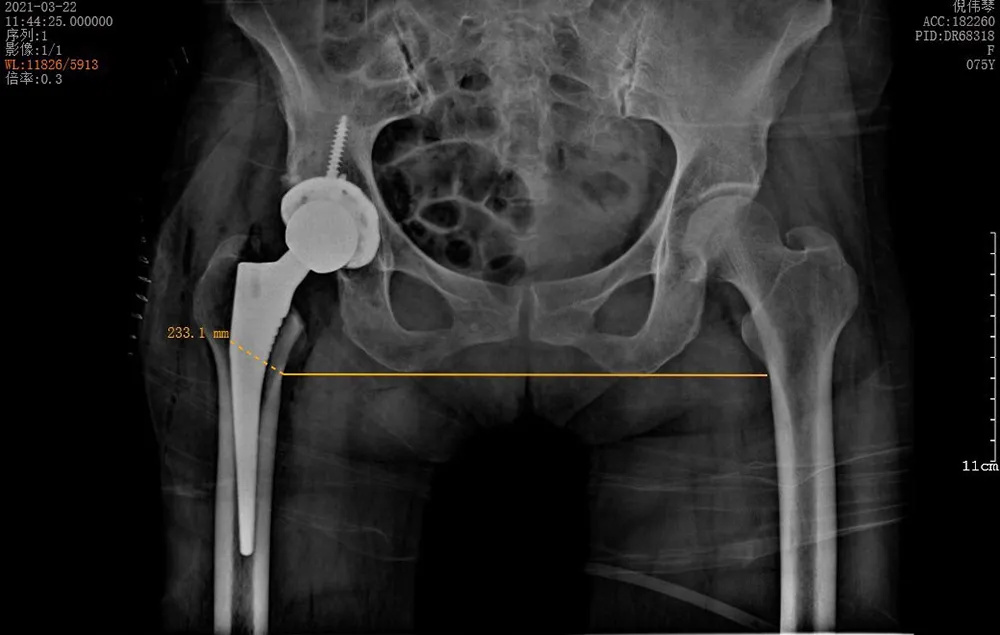

3月22日,在將倪阿姨的身體調(diào)整到最佳狀態(tài)并完善所有術(shù)前準(zhǔn)備之后,羅軍團(tuán)隊(duì)為她進(jìn)行了手術(shù)。術(shù)中發(fā)現(xiàn)其股骨頭完全壞死,而且患者的骨質(zhì)疏松嚴(yán)重,所有操作必須十分小心,幸好有精準(zhǔn)的AI-HIP術(shù)前規(guī)劃,手術(shù)歷時1個小時就成功完成,全程出血不到50ml。

↑術(shù)后雙下肢完全等長